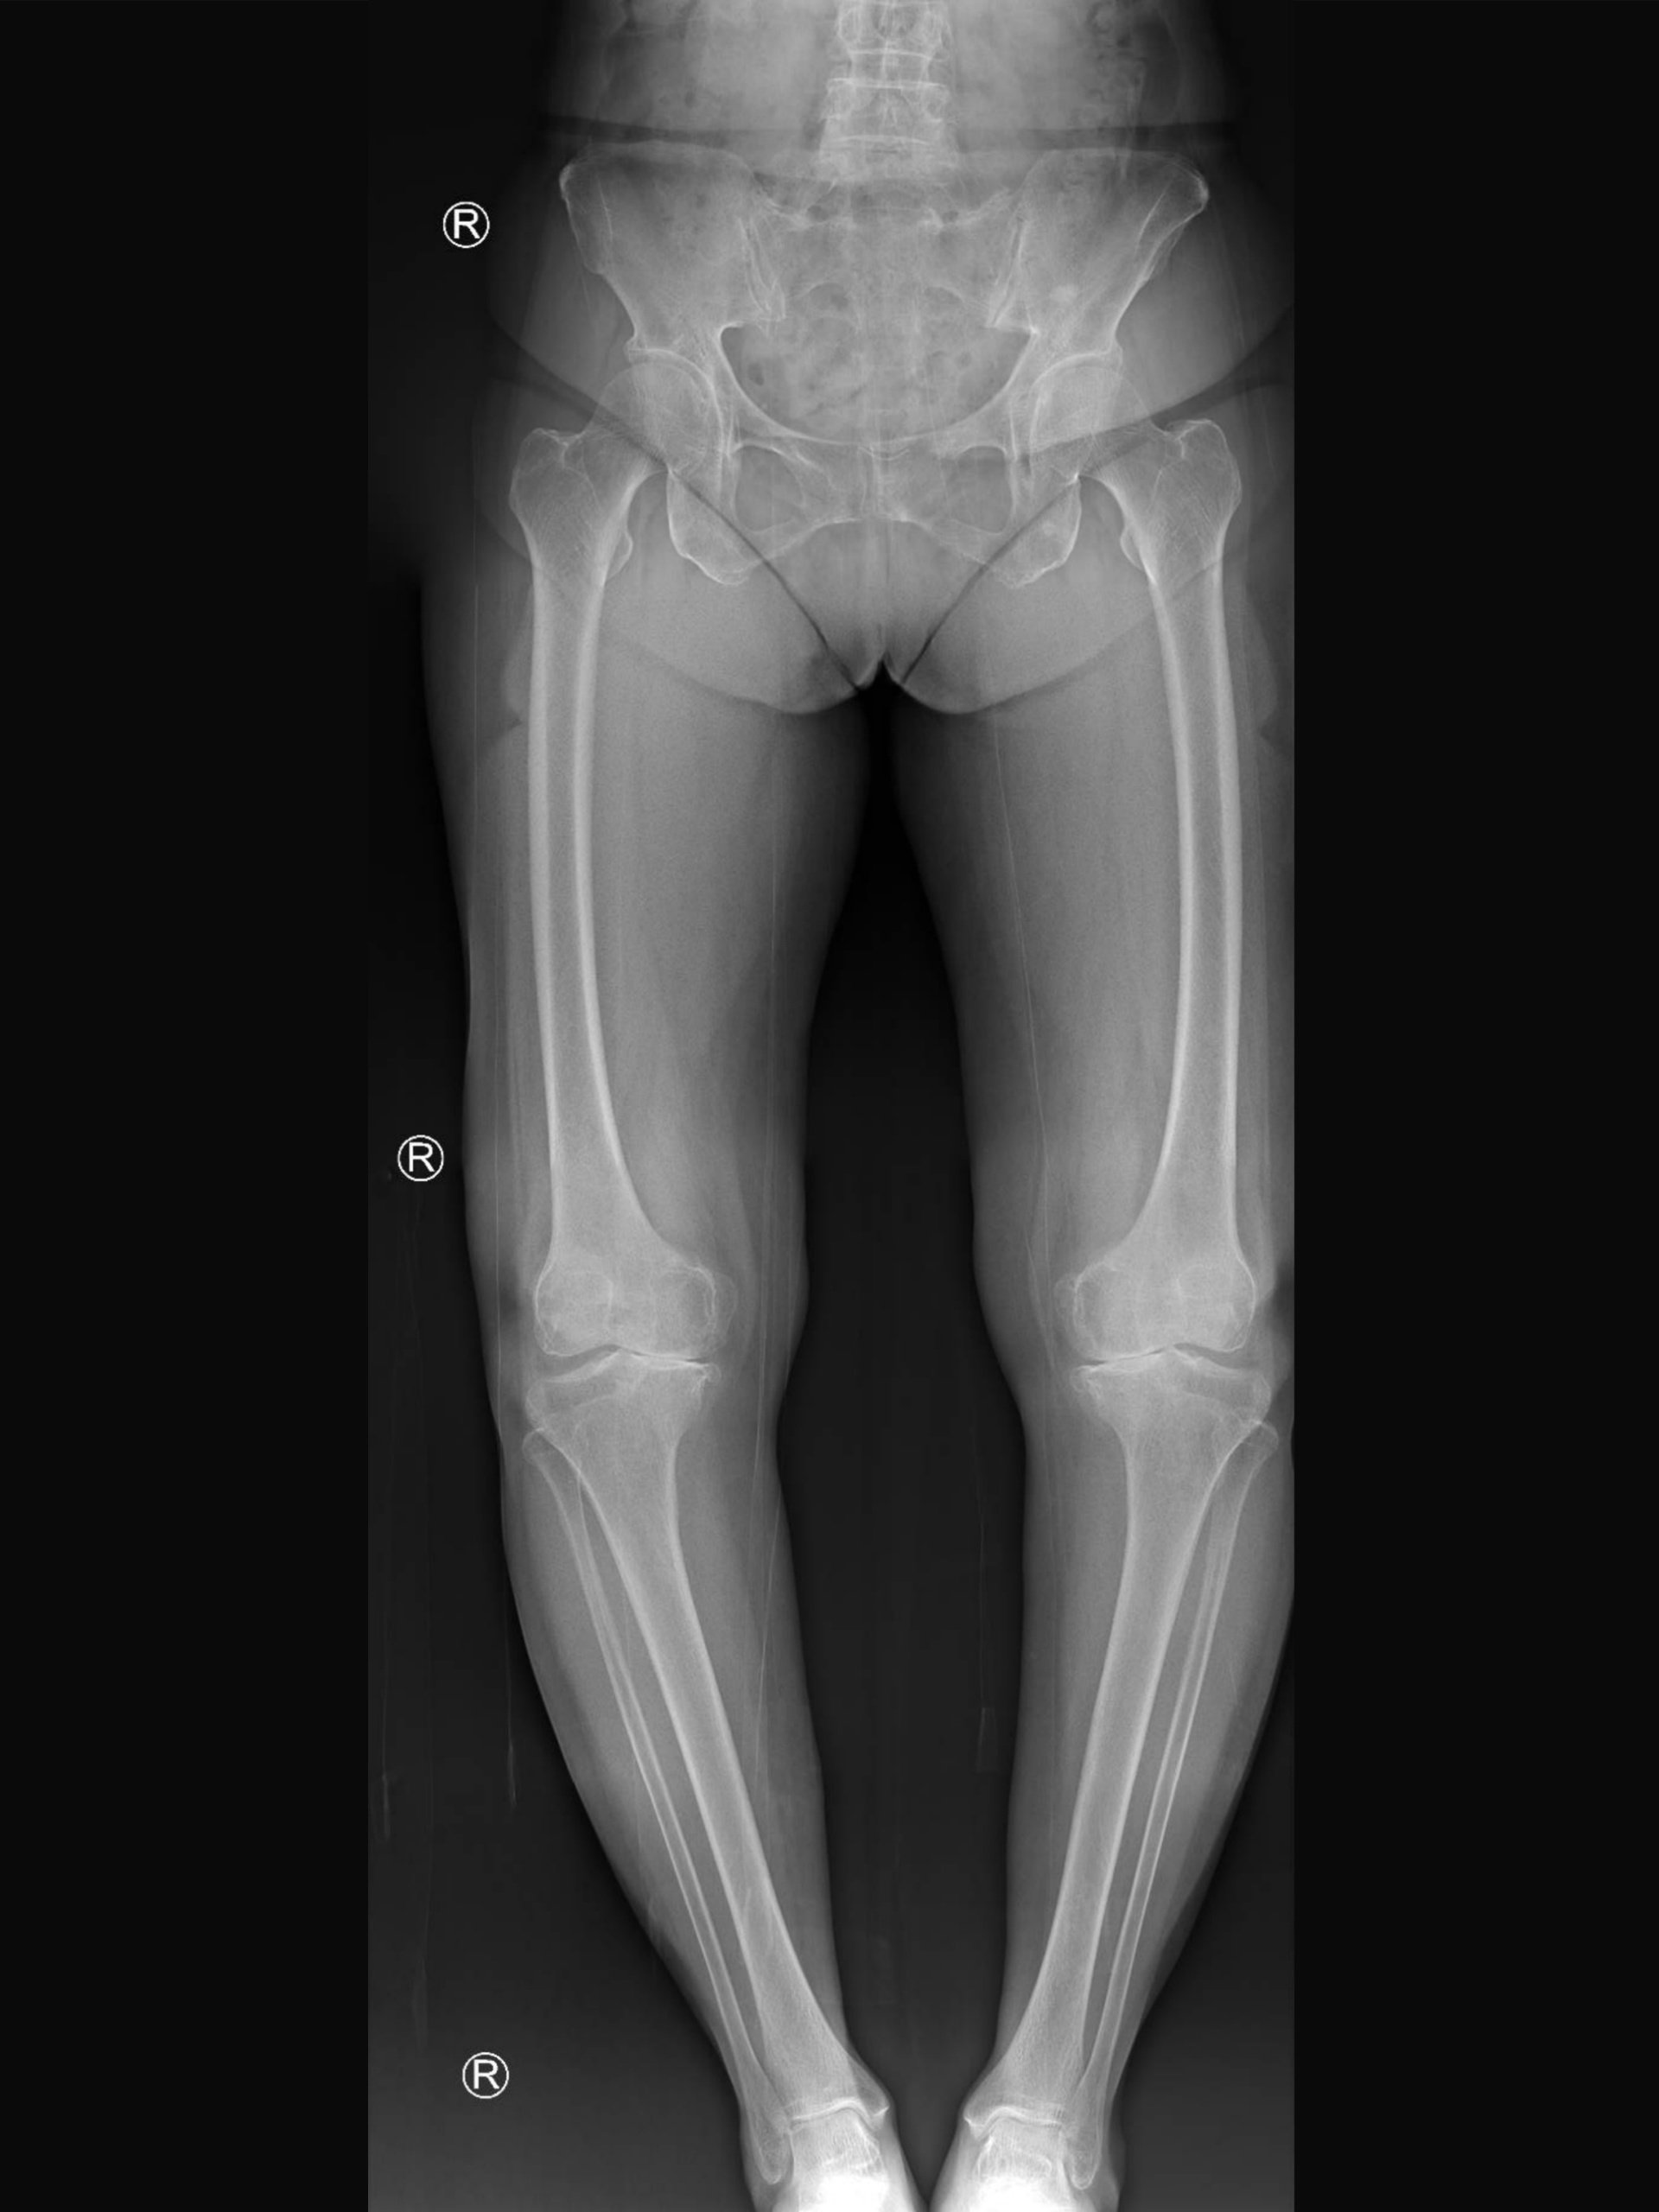

- Ακτινογραφίες γόνατος:

- Δείχνει το βαθμό και τη θέση της φθοράς μέσα στο γόνατο και την παραμόρφωση γύρω από το γόνατο

- Ακτινογραφίες ευθυγράμμισης όλου του κάτω άκρου:

- Ακτινογραφίες και των δύο κάτω άκρων σε όρθια θέση από τη λεκάνη ως την ποδοκνημική

- Από τις ακτινογραφίες ευθυγράμμισης όλου του κάτω άκρου, ο ορθοπαιδικός θα μπορεί να υπολογίσει τη θέση και τον βαθμό παραμόρφωσης και τον απαιτούμενο βαθμό διόρθωσης

- Αυτό θα βοηθήσει στη συνέχεια να προσδιοριστεί:

- Πού να πραγματοποιηθεί οστεοτομία (κνήμη ή μηρός)

- Ποιος τύπος οστεοτομίας θα εφαρμοστεί (ανοιχτής ή κλειστής σφήνας)